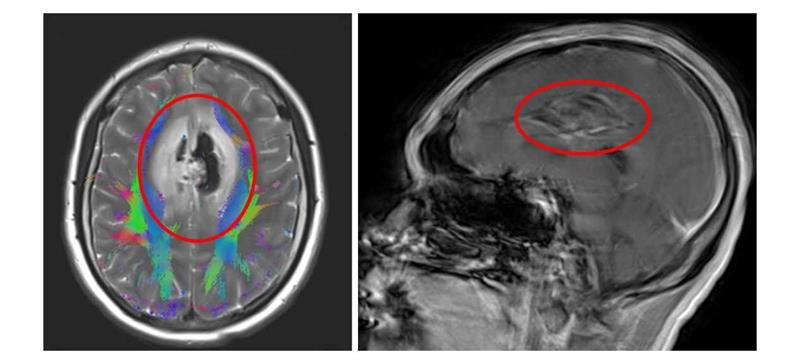

1月14日下午,東莞一位懷孕32周的鄧女士突然出現(xiàn)無法說話,四肢無力,并伴有低熱等癥狀,緊急送醫(yī)后急查MRI平掃提示“雙側(cè)額葉及中線區(qū)占位性病變伴腦水腫、腦疝”。高危妊娠合并顱腦腫瘤,病情瞬息萬變——腦疝風(fēng)險(xiǎn)與早產(chǎn)危機(jī)并存,一場關(guān)乎兩條生命的救治迫在眉睫。

巨大腦腫瘤病變部位

患者到院后,孫劍院長指示醫(yī)務(wù)處全程跟進(jìn),神經(jīng)外科中心學(xué)術(shù)帶頭人漆松濤主任醫(yī)師、科室主任張喜安主任醫(yī)師、亞專業(yè)組長黃廣龍主任醫(yī)師等迅速組織全院多學(xué)科會(huì)診。“腫瘤位于大腦深部,已引起神經(jīng)功能損傷,顱內(nèi)壓升高,必須盡快手術(shù)減壓。”漆松濤提到,“但妊娠晚期手術(shù)猶如‘刀尖起舞’,需在去除病灶的同時(shí),全力守護(hù)母嬰安全。”

緊接著,神經(jīng)外科中心漆松濤、黃廣龍主任醫(yī)師團(tuán)隊(duì)在黃熒光引導(dǎo)與神經(jīng)內(nèi)鏡輔助下,于顯微鏡下展開精細(xì)操作,成功將血供豐富、邊界不清的腫瘤完整切除,并最大程度地保護(hù)了正常的腦組織功能。